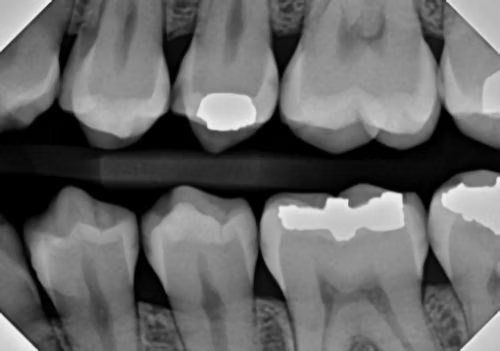

The first diagnostic innovation is AI-supported radiographic interpretation

Rather than the discernment of various shades of gray resting on the shoulders of the clinician, who may or may not have adequate time in every different clinical scenario, decay is highlighted by the computer AI software itself, making it a bit more difficult to miss a lesion and highly documenting the degree of enamel or dentin penetration of the lesion.